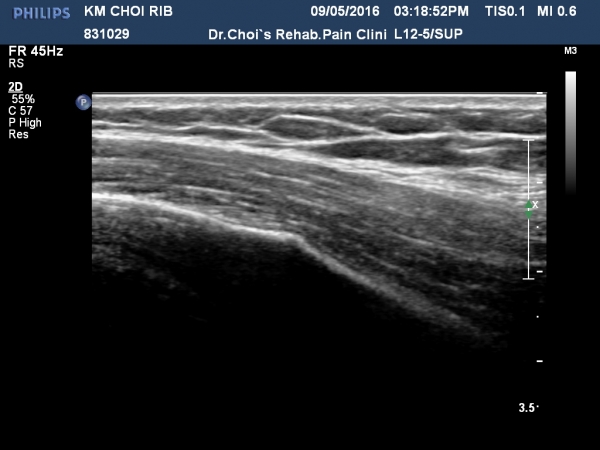

ÃÊÁø ½Ã °¥ºñ»À ÃÊÀ½ÆÄ°Ë»ç¿¡¼­ ÇÇÁú°ñ ¤·³à¼Ó¼º ¼Ò½ÇÀº º¸ÁöÁö ¾ÊÀ¸³ª

±æºñ»À Ç¥Ãþ¿¡ ±¹¼ÒÀûÀÎ ¿¬ºÎÁ¶Á÷ ºÎÁ¾ÀÌ °üÂûµÈ´Ù(»çÁø 1, 2, 3, 4).